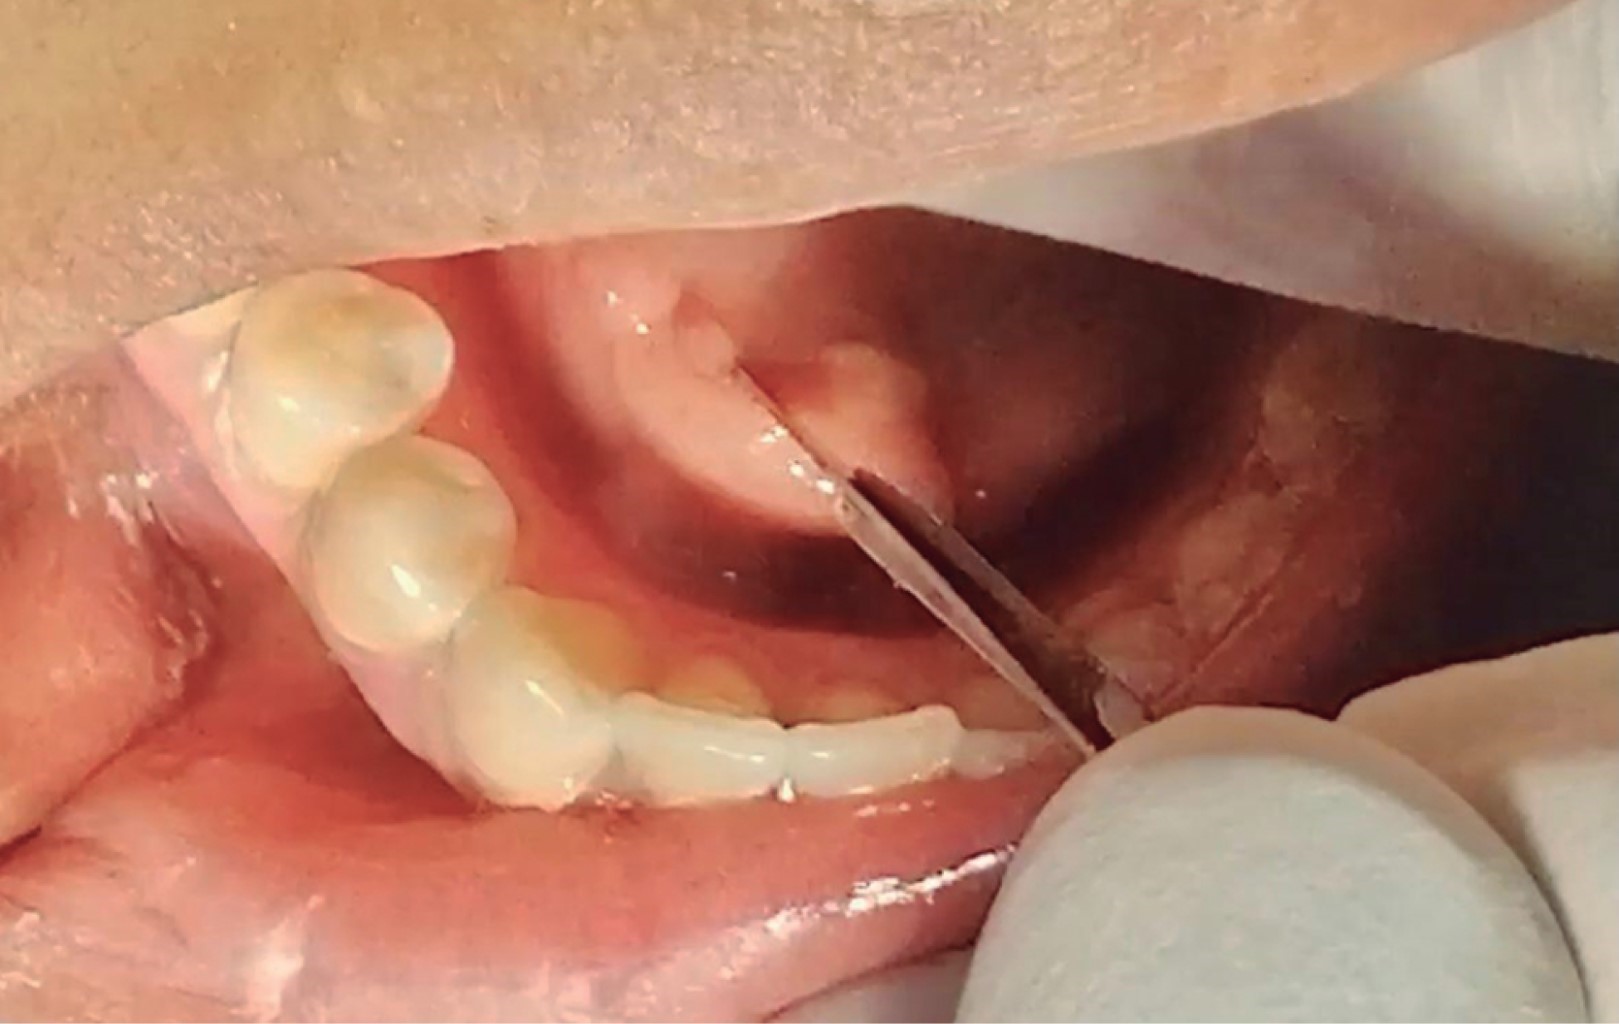

Se presenta paciente femenino de 37 años de edad, con antecedentes patológicos personales y heredofamiliares negados, su motivo de consulta "inflamación en piso de boca". La paciente refiere aumento de volumen en piso de boca de lado derecho de cinco días de evolución, asimismo ardor y dolor al comer. Acude al médico general el cual prescribe antibiótico y analgésicos con un presunto diagnóstico de absceso, la paciente no presentó mejoría asociada a dicha terapéutica médica. A la exploración clínica extraoral, durante la inspección se aprecia una asimetría asociada a un aumento de volumen en la región submandibular (triángulo digástrico), a la palpación se percibe dicho aumento indurado y la paciente refiere dolor. De forma intraoral se aprecia un aumento de volumen de 3 cm en el piso de boca, asociado al conducto de Wharton del lado derecho, con una mucosa inflamada, eritematosa, con un punto blanco compatible con una fístula. A la palpación se encuentra indurado y con dolor (Figura 2). En la maniobra de digitopresión para ordeñar la glándula submandibular, se pudo apreciar salida de escaso material purulento el cual drenaba a través de la fístula, sin permeabilidad ni drenaje de la carúncula. La radiografía panorámica demostró un área radiopaca de forma ovalada en el piso de la boca, cerca de los cuellos de los premolares y en la región de los dientes anteriores inferiores. Se solicitó una tomografía computarizada para una mejor delimitación de la lesión, la cual reveló un cuerpo hiperdenso de alrededor de 30 mm en la región submandibular derecha (Figura 3). Los hallazgos clínicos e imagenológicos llevaron al diagnóstico de sialolito asociado al conducto submandibular. Debido al tamaño y la localización del cálculo, se optó por la extirpación quirúrgica del sialolito de manera ambulatoria con la preservación de la glándula submandibular.

Figura 2